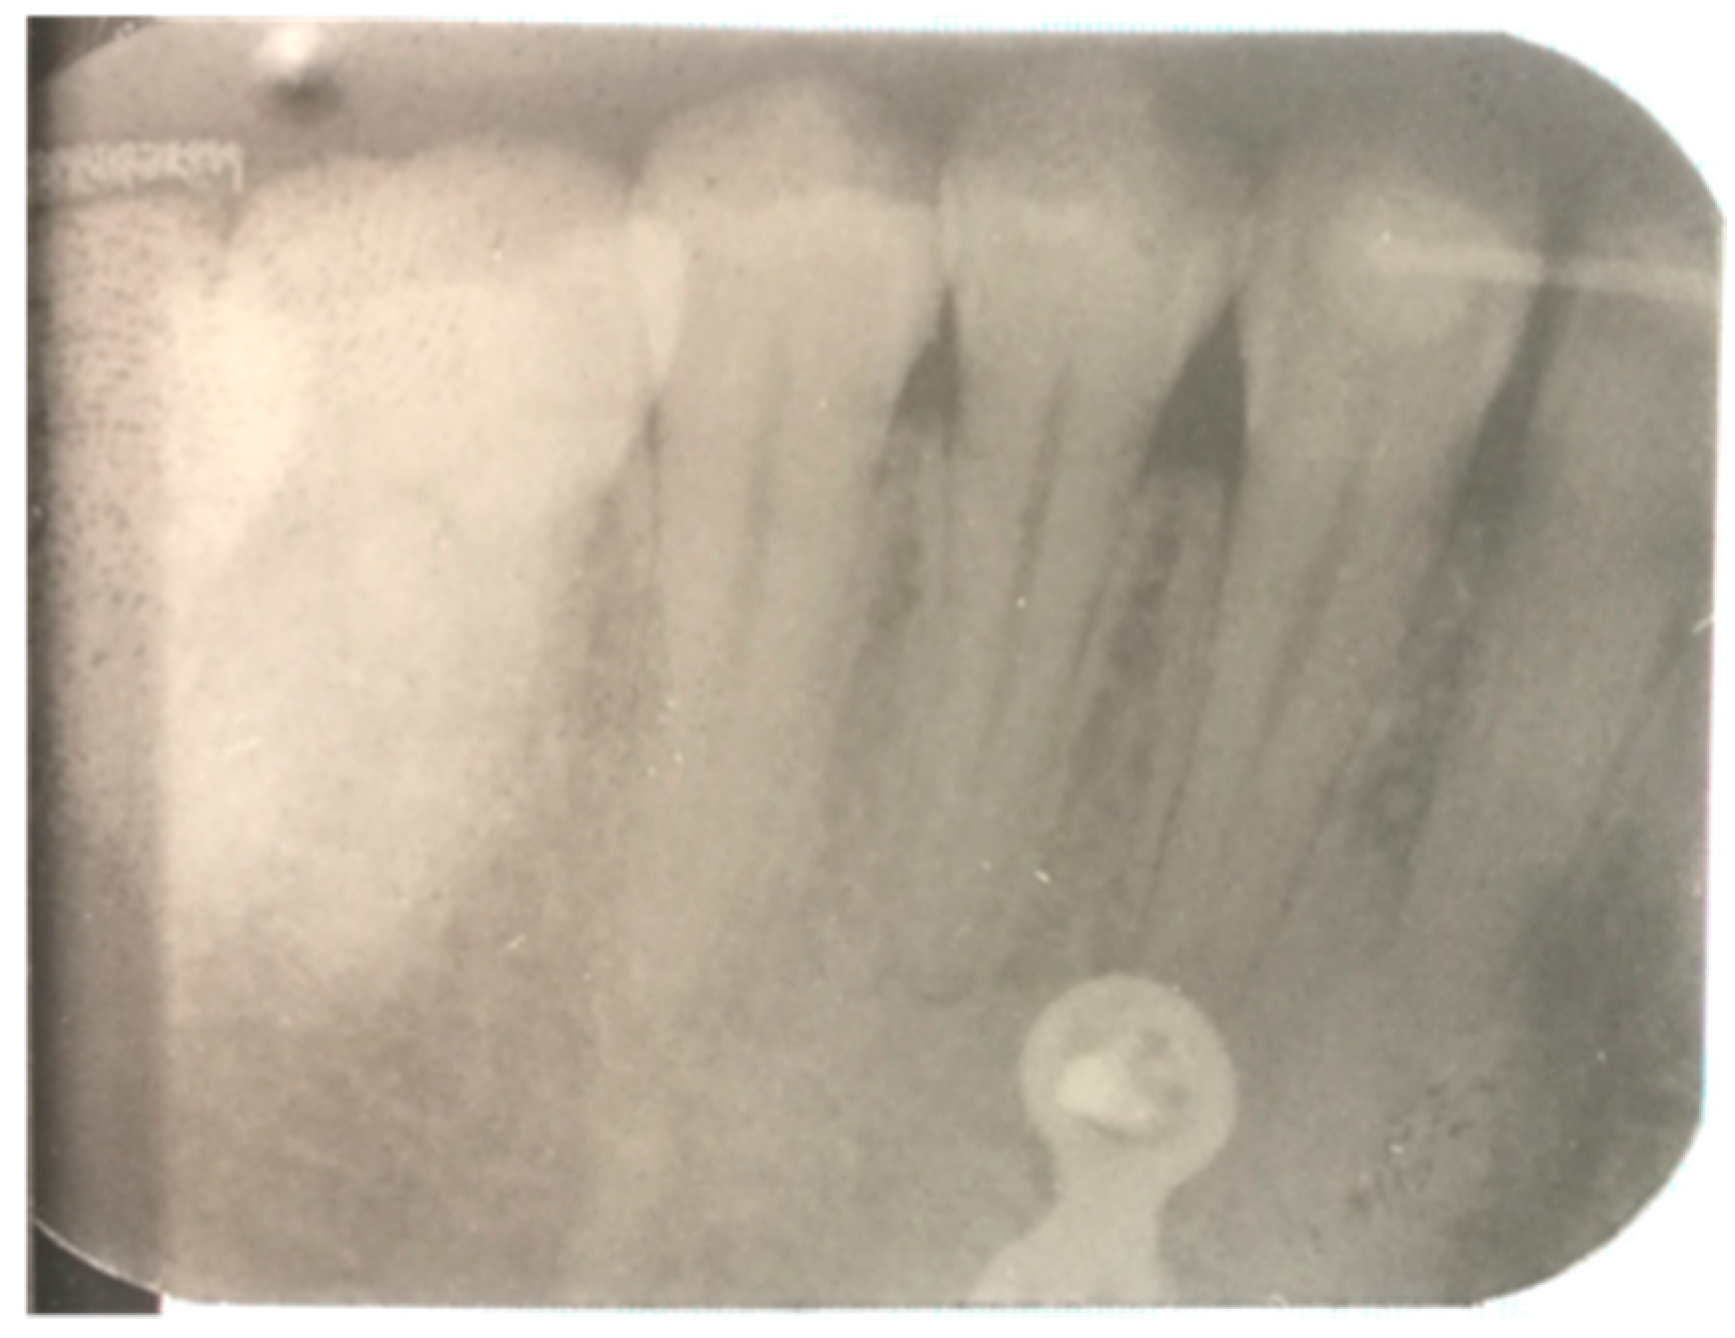

| Dental Discromies and Pulpal Necrosis | 4 | 6.89 |